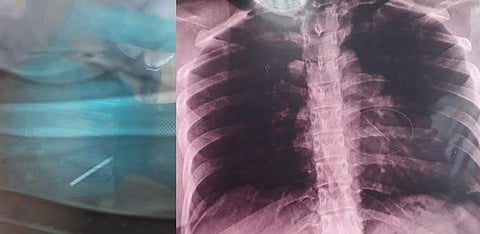

இந்நிலையில் தற்போது கர்ப்பிணியாக உள்ள சசிகலாவுக்கு சமீபத்தில் நெஞ்சில் கடுமையான வலி ஏற்படவே, அருகில் உள்ள தனியார் மருத்துவமனையில் சிகிச்சைக்காகக் காட்டியுள்ளனர். அப்போது மீண்டும் அவருக்கு எக்ஸ்ரே எடுக்கப்பட, அந்த எக்ஸ்ரேவில் சசிகலாவின் கையில் இருந்து அகற்றப்பட்டதாகக் கூறப்பட்ட உடைந்த ஊசி தற்போது அவரது நெஞ்சுப் பகுதியில் இருப்பது தெரிய வந்திருக்கிறது.